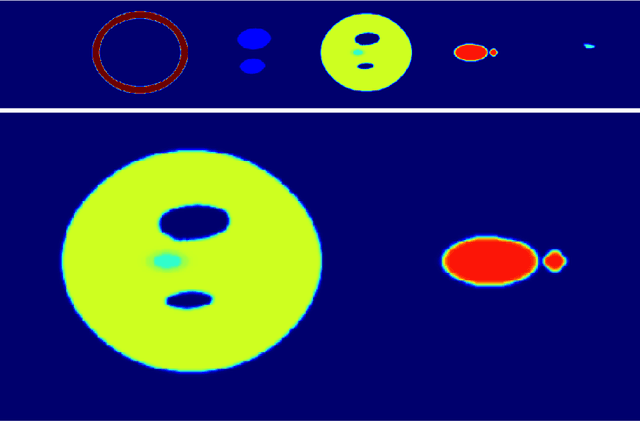

It is a common practice in multimodal medical imaging to undersample the anatomically-derived segmentation images to measure the mean activity of a co-acquired functional image. This practice avoids the resampling-related Gibbs effect that would occur in oversampling the functional image. As sides effect, waste of time and efforts are produced since the anatomical segmentation at full resolution is performed in many hours of computations or manual work. In this work we explain the commonly-used resampling methods and give errors bound in the cases of continuous and discontinuous signals. Then we propose a Fake Nodes scheme for image resampling designed to reduce the Gibbs effect when oversampling the functional image. This new approach is compared to the traditional counterpart in two significant experiments, both showing that Fake Nodes resampling gives smaller errors.